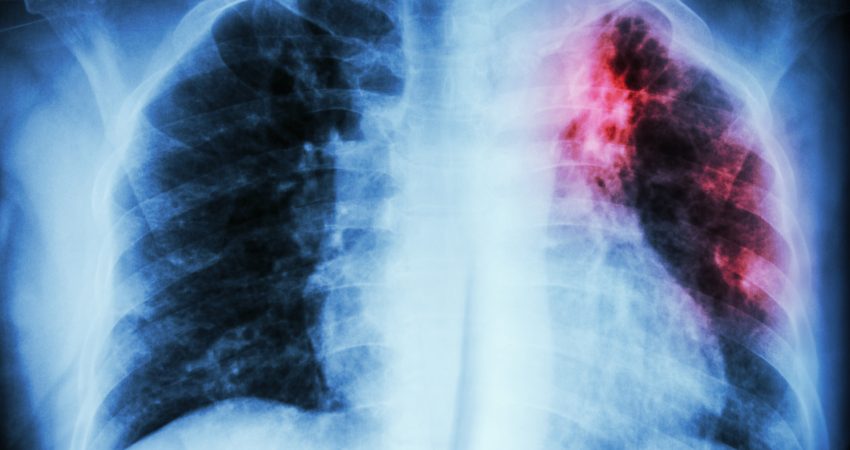

Mënyrat për të diagnostikuar sëmundjen janë me anë të radiografisë dhe përdorimi i testit të tuberkulozit, i cili jo vetëm që përcakton gjendjen sëmundjen, por edhe rezistencën ndaj medikamentit kryesor të tuberkulozit siç, është rafampicina.

Sipas të dhënave të Organizatës Botërore të Shëndetësisë tuberkulozi është në dy gjendje, pozitiv (infektues për të tjerët) dhe negativ. Ndërsa, simptomat më të shpeshta të tuberkulozit janë kollë dhe pështymë me gjak, dhimbje kraharori, dobësi, humbje në peshë, temperaturë dhe djersitje natën.